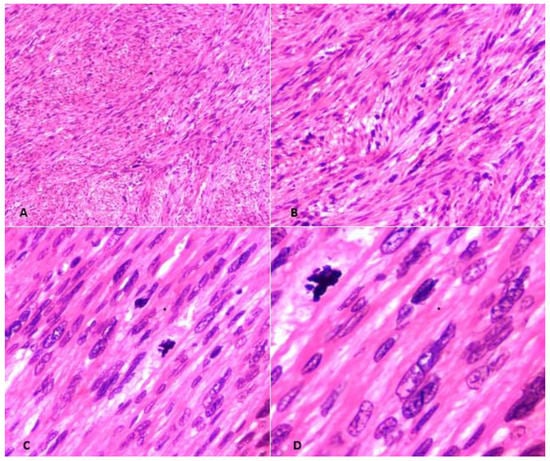

3. Anatomopathological Features

- smooth muscle tumors with focal/multifocal or diffuse cytological atypia (moderate-to-severe), lacking coagulative tumor necrosis and 6–9 mitoses per 10 HPFs (2–4 mitoses/mm2).

- Tumors that lack cytological atypia or raised mitotic count but having unequivocal coagulative tumor necrosis.

- Tumors with elevated mitotic count (>15 mitoses per 10 HPFs or >6 mitoses/mm2) but lacking coagulative tumor necrosis or cytological atypia.

- Tumors with uncertain mitotic count but having diffuse cytological atypia (moderate-to-severe).